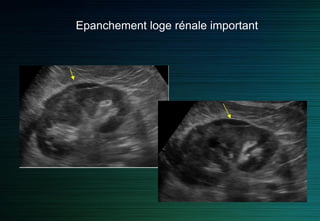

Epanchement loge rénale important

Ne pas confondre avec un épanchement dans la loge de Morison